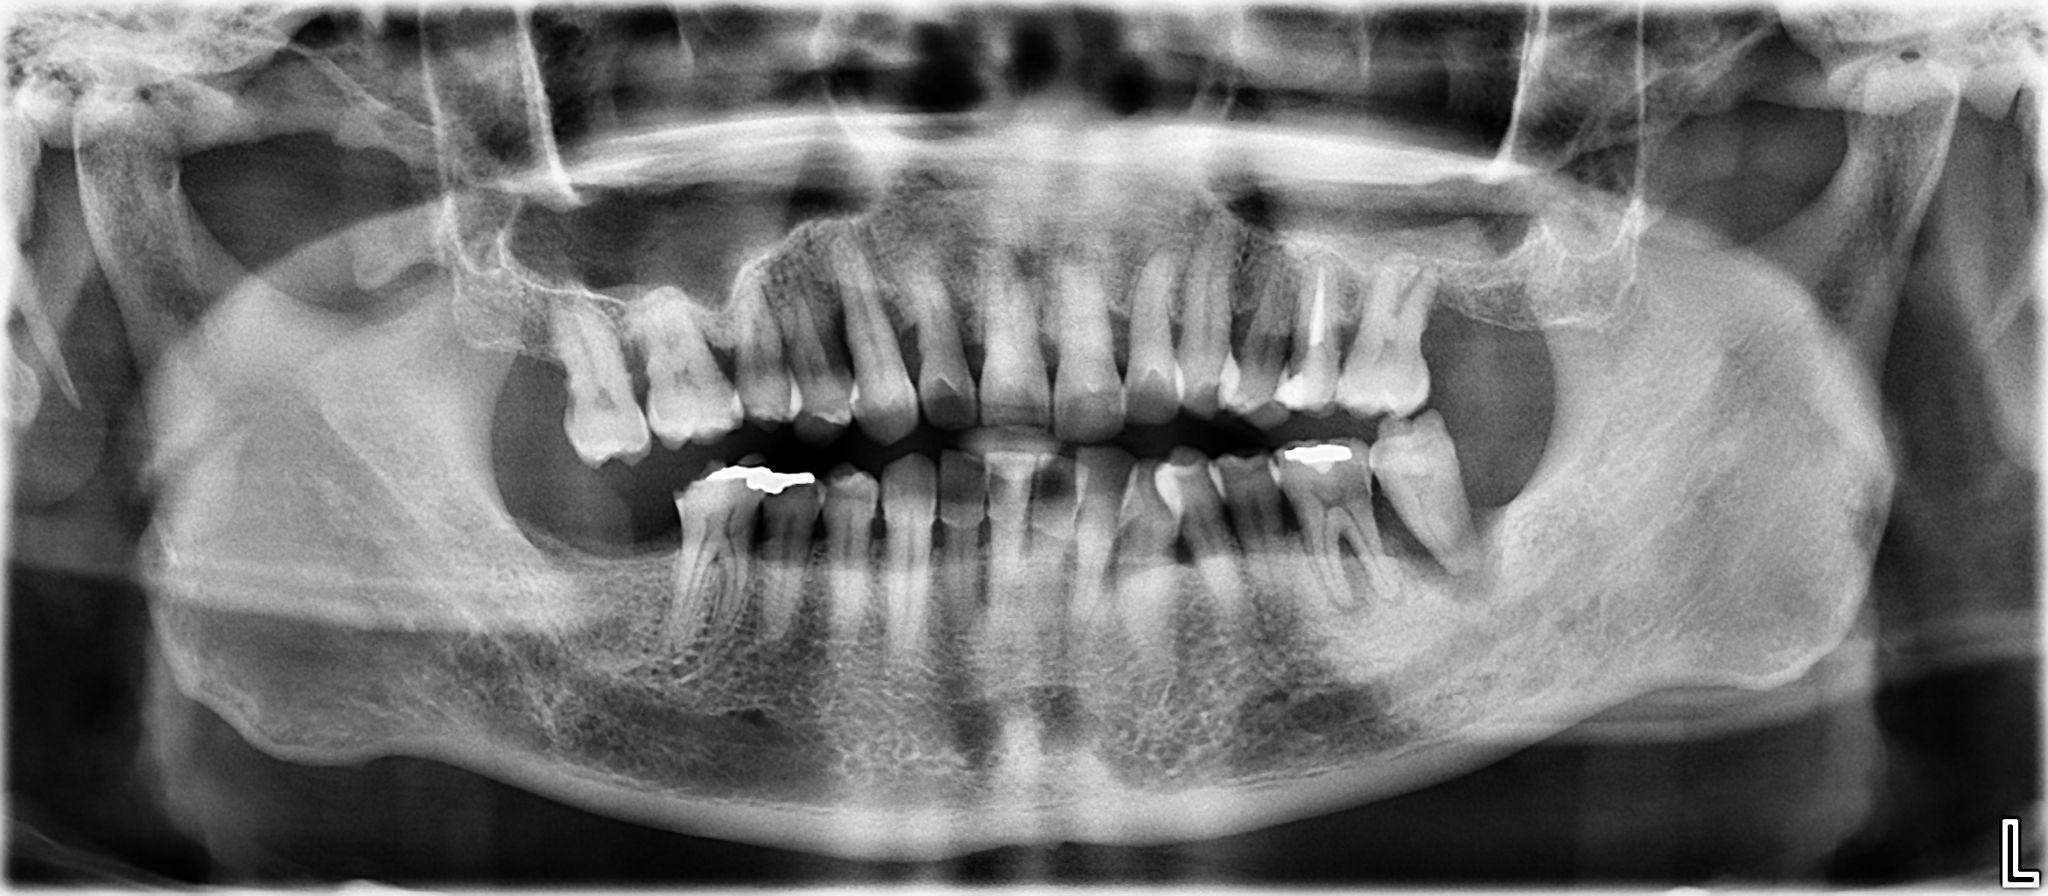

1. What options can be selected for the first quadrant of this panoramic X ray?

2. What options can be selected for the second quadrant of this panoramic X ray?

3. What options can be selected for the third quadrant of this panoramic X ray?

4. What options can be selected for the forth quadrant of this panoramic X ray?